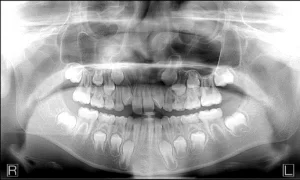

There is a growing desire by health care facilities to add panoramic dental x-ray modalities to their capabilities. The main reasons for this are a combination of the panoramic x-ray’s broad diagnostic capabilities along with it’s low cost and low radiation relative to other traditional medical imaging modalities. Here are three common applications:

1. Emergency rooms and urgent care facilities value the targeted anatomy and field of view as be an ideal modality to assess facial trauma. For example, as more of these facilities are seeing patients with severe or emergency dental ailments, the staff values the panoramic dental modalities to help determine whether the patient should be referred to a dentist or to another specialist.

2. Surgical centers used by dental surgeons that utilize the panoramic image to capture pre and post-surgery x-rays.

3. Self-contained facilities, like military bases, prisons and native american reservations, that must provide full health care to a specific population. In these scenarios, the facility values the multi-purpose modality that not only can provide dental care, but also offer the broader capabilities mentioned above.